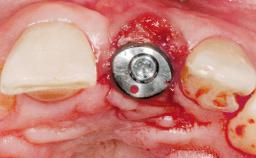

Immediate Flapless Placement of an Implant in a Maxillary Left Central Incisor Site

A 29-year-old female patient presented for treatment to replace the upper left central incisor tooth with an implant- supported restoration. The tooth had been intermittently symptomatic for the previous 12 months. The tooth had originally suffered trauma about 15 years previously. Several endodontic treatments had been performed, including an apicectomy procedure to retain the tooth. The patient was healthy and a non-smoker. She had reasonable expectations in regard to esthetic outcomes and the risk of marginal tissue recession following treatment. At medium smile, the gingival margins of the upper teeth were visible, with a display of 3 to 4 mm of the gingival margins. Gingival recession of tooth 21 and a discrepancy in the gingival levels between teeth 11 and 21 was observable during normal speech and smile.

| Placement Protocol | Immediate implant placement |

| Tooth Site | Maxillary incisor or canine |

| Socket Morphology | Single-root socket |

| Socket Integrity | Damage to one or more bone walls |

| Bone Volume | Damage to one or more socket walls |